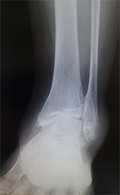

変形性足関節症

変形性足関節症は、足関節の表面に覆われている軟骨がすり減ってしまう疾患です。骨折や繰り返す捻挫など外傷によって起こることが多いと言われています。

歩行時に軟骨のすり減っている部分に疼痛が生じます。病態が進行すると、外観上も足の変形が認められます。

痛みが強い場合や変形が強い場合は、主に関節固定術を行います。適応となる患者さんは限られていますが、足関節の可動域を温存するため、脛骨低位骨切り術や人工足関節置換術を行うこともあります。

単純レントゲン写真

(矢印)